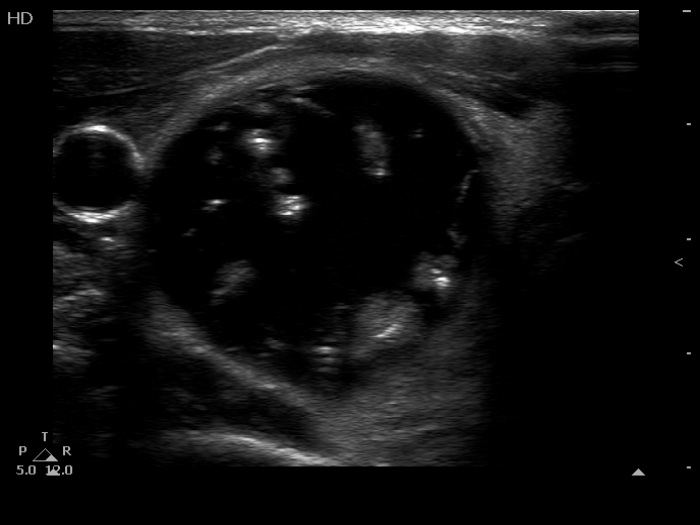

The composition of the nodule - case 1511 (ultrasonographic picture 3)

Right lobe, another transverse scan. The echogenic figures within the solid parts are partly caused by posterior back wall enhancement.